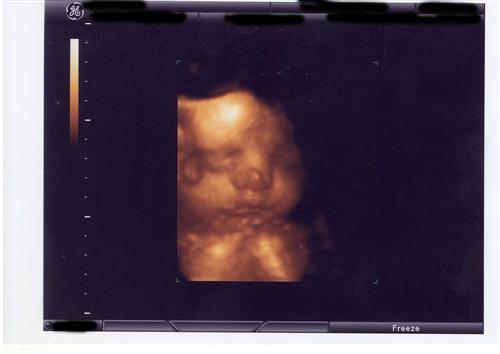

I had a 32 week ultrasound and unfortunately baby E was not cooperating and decided to put her/his arm over the face the whole time, no matter what we did. So the pictures are not the best, but tell me what you think! My DH is convinced it is a girl. We shall see!

Very cute Katie! I think you are having a for some reason, but I can't tell anything but a cute face from your pics!

what awesome pics!! how cute! i say

OH what great pics i say baby

Just going by the last pic (which is adorable by the way!) I am going to say